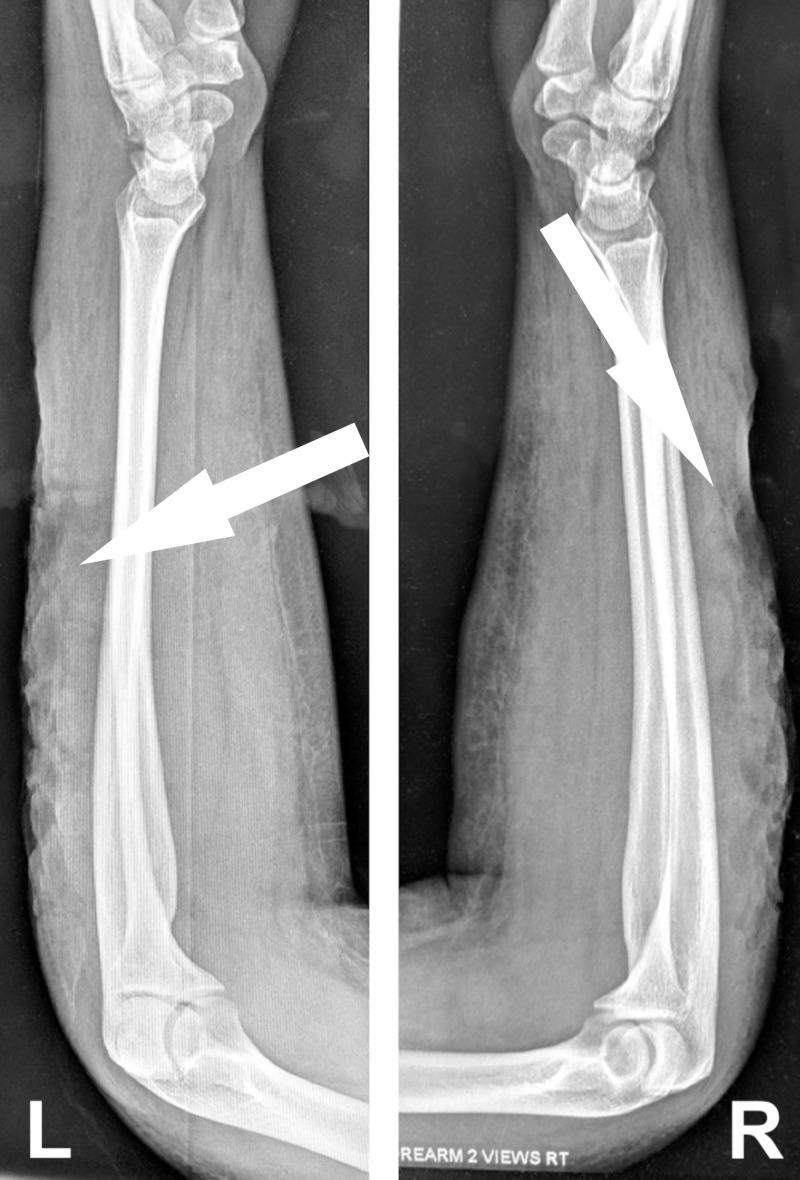

The authors present a case of severe skin necrosis resulting from injecting heroin laced with a substance known as "Rizzy" powder. This powder is a toxic substance used to color the petals of plants. This report reviews how to manage the complications of such adulterated heroin.

作者报告了一例因注射掺有“Rizzy”粉末的海洛因导致严重皮肤坏死的病例。这种粉末是一种用于给植物花瓣上色的有毒物质。本报告回顾了如何处理此类掺假海洛因的并发症。